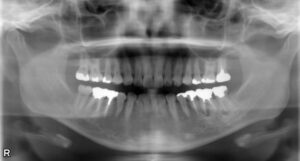

左下第一大臼歯欠損症例

BEFORE AFTER 39歳女性/下顎1本欠損/インプラント埋込手術 【治療内容】 左下の腫れが主訴でご来院された患…